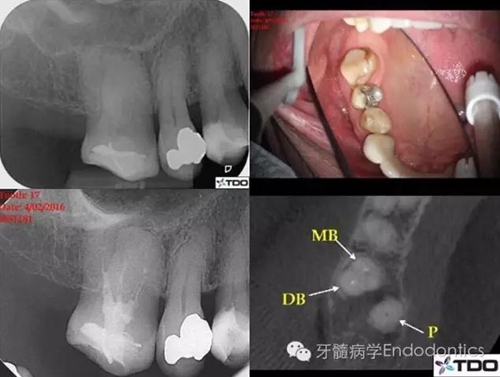

該上頜磨牙盡管位于第一磨牙的位置,但是解剖結(jié)構(gòu)類似第二磨牙。初診時(shí)醫(yī)生尋找到3個(gè)根管,近中頰根具有粗大、卵圓形的根管口,常見于具有融合根的上頜第二磨牙。醫(yī)生為確定近中頰根僅有一個(gè)根管,氫氧化鈣封藥后拍攝CBCT。CBCT上近頰根似乎只有一個(gè)居中的根管,醫(yī)生不確定MB根管是否在下段存在二分叉(圖1)。

圖1